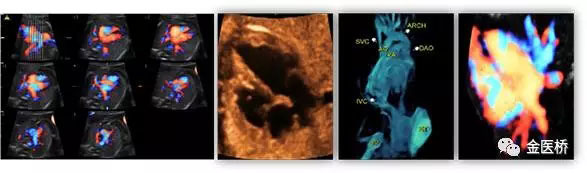

胎兒心臟超聲又名胎兒超聲心動圖,是一種無創(chuàng)、安全的影像學檢查,也是胎兒期唯一有效的能夠顯示胎兒心臟結(jié)構(gòu)、血流及評估心臟功能的影像學手段,在產(chǎn)前及時診斷,隨診,預(yù)后判斷至關(guān)重要,不可替代。

一般情況下,一個詳細完整的胎兒心臟彩超檢查大約需要30-60分鐘。